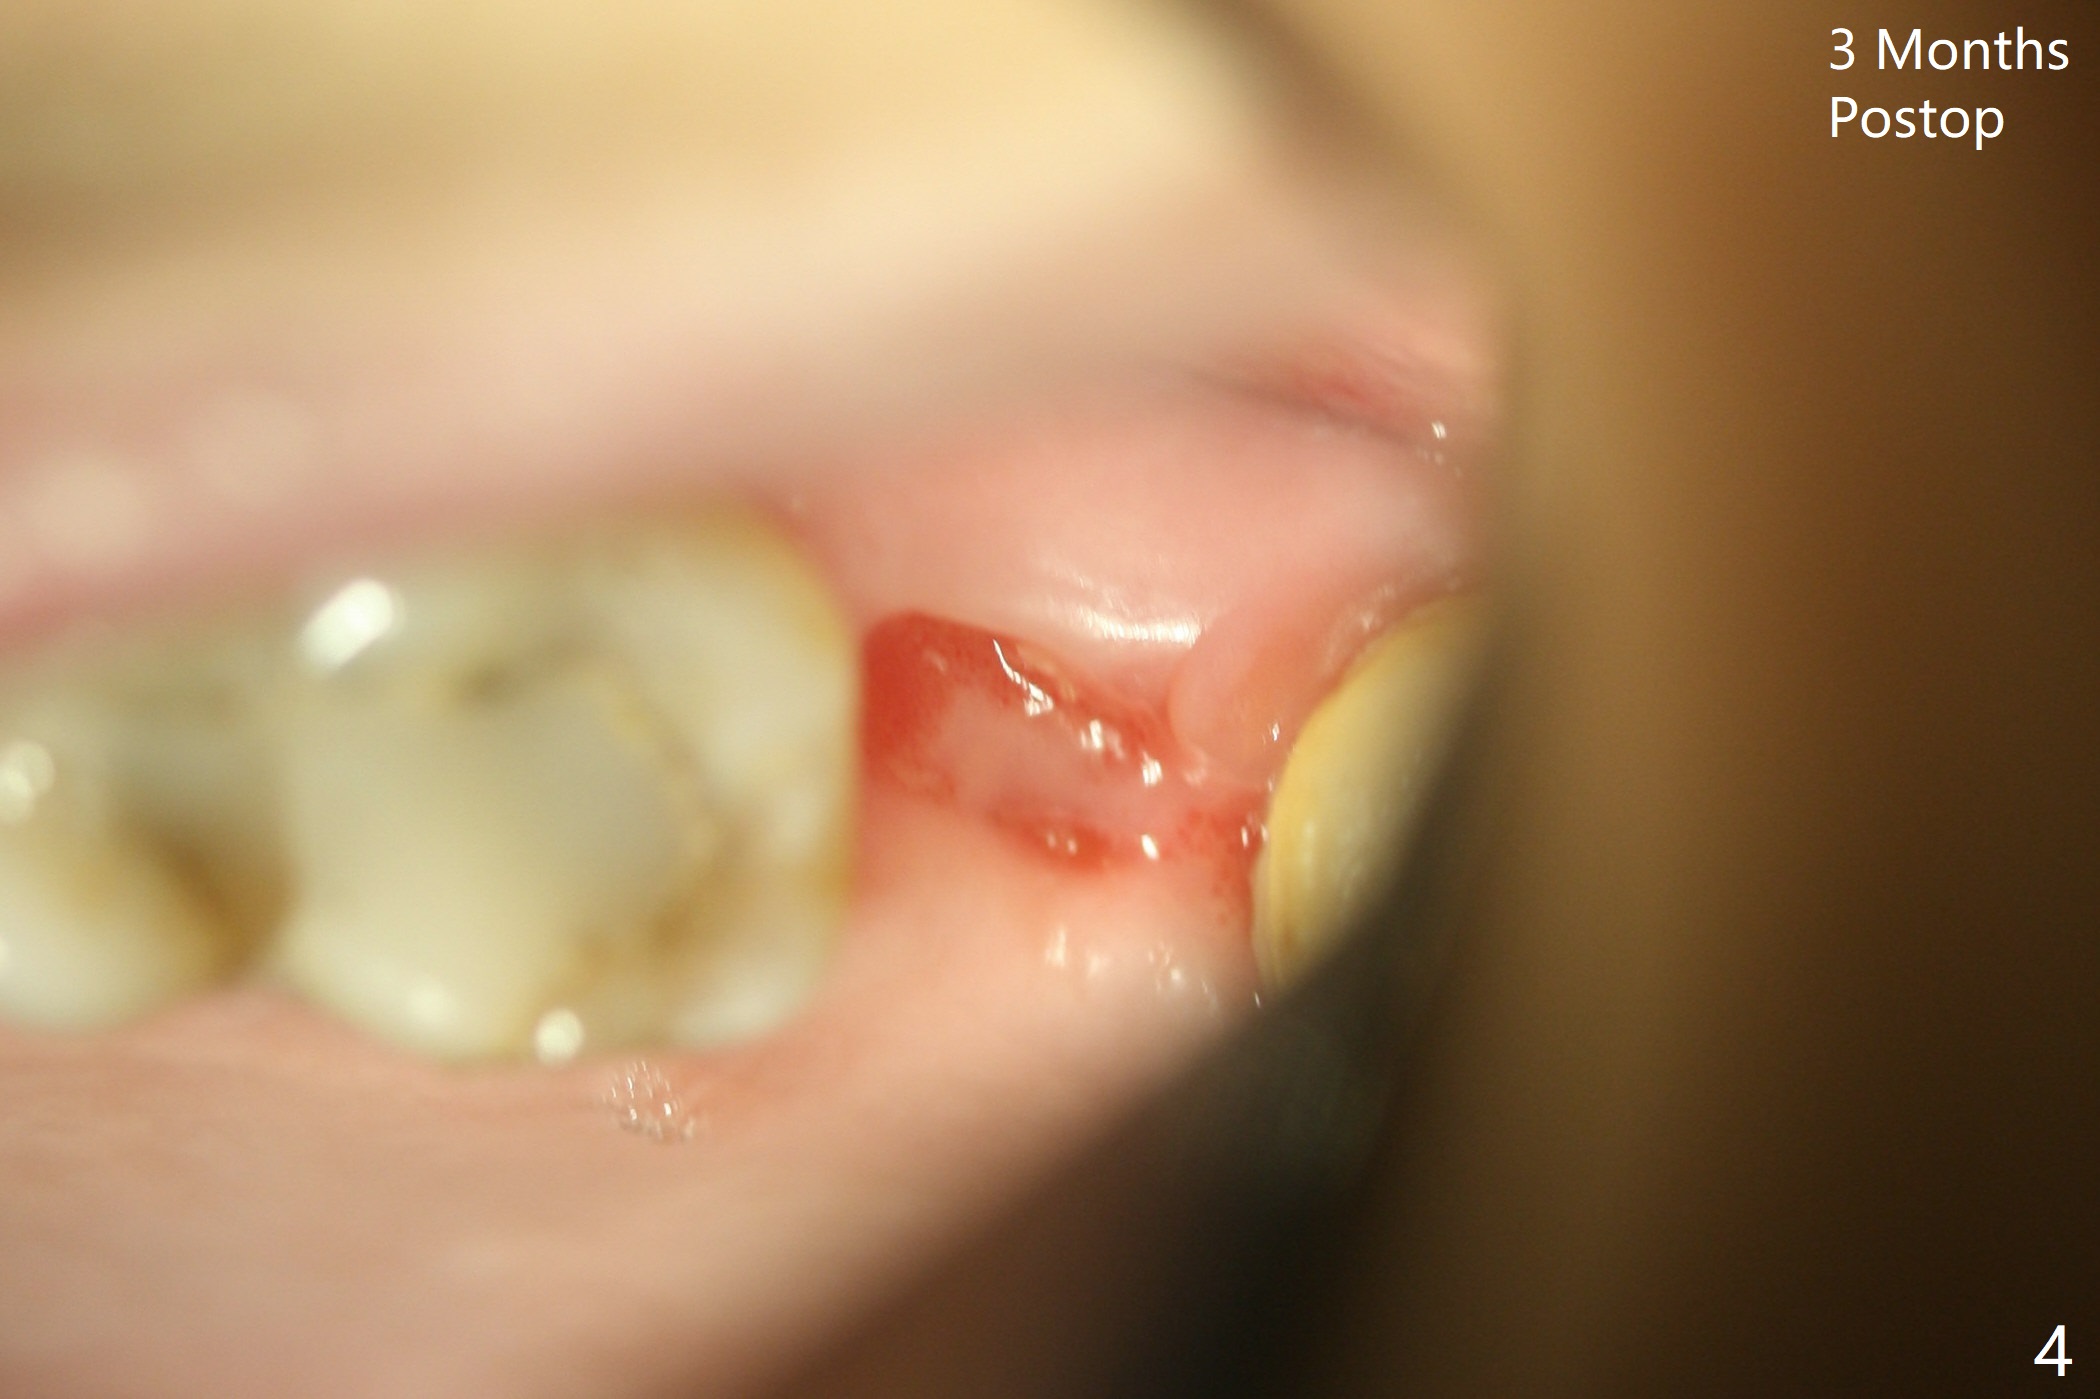

The healed socket appears to have been shrunken buccopalatally 3 months postop (Fig.4), probably due to the absence of an abutment and a provisional.